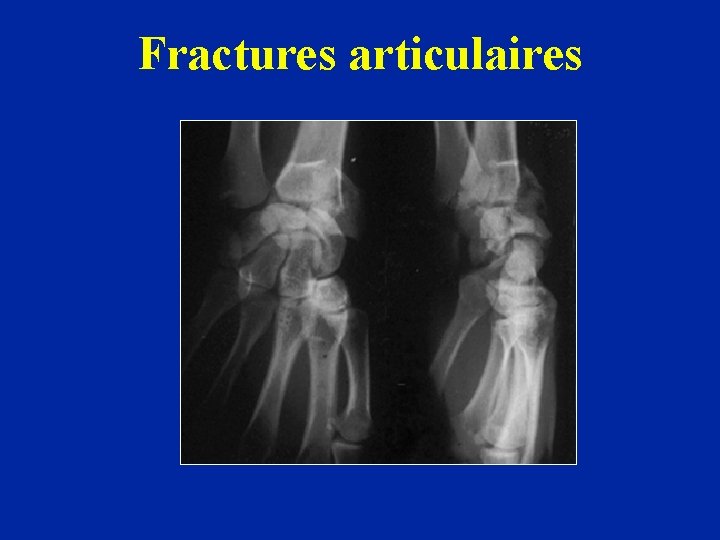

Fractures articulaires